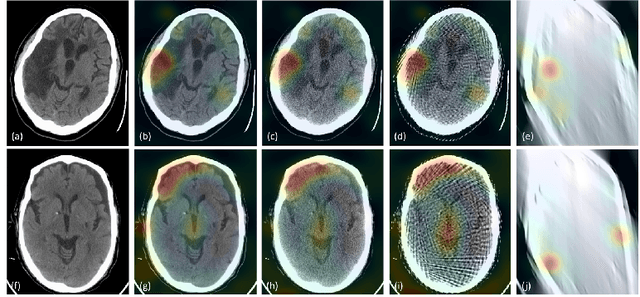

Abstract:Automated medical image classification with convolutional neural networks (CNNs) has great potential to impact healthcare, particularly in resource-constrained healthcare systems where fewer trained radiologists are available. However, little is known about how well a trained CNN can perform on images with the increased noise levels, different acquisition protocols, or additional artifacts that may arise when using low-cost scanners, which can be underrepresented in datasets collected from well-funded hospitals. In this work, we investigate how a model trained to triage head computed tomography (CT) scans performs on images acquired with reduced x-ray tube current, fewer projections per gantry rotation, and limited angle scans. These changes can reduce the cost of the scanner and demands on electrical power but come at the expense of increased image noise and artifacts. We first develop a model to triage head CTs and report an area under the receiver operating characteristic curve (AUROC) of 0.77. We then show that the trained model is robust to reduced tube current and fewer projections, with the AUROC dropping only 0.65% for images acquired with a 16x reduction in tube current and 0.22% for images acquired with 8x fewer projections. Finally, for significantly degraded images acquired by a limited angle scan, we show that a model trained specifically to classify such images can overcome the technological limitations to reconstruction and maintain an AUROC within 0.09% of the original model.